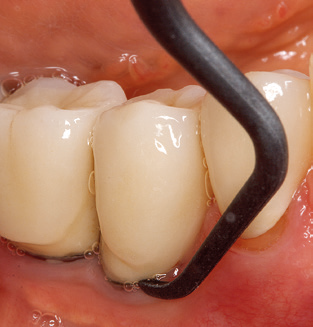

Das aktuelle Arbeitskonzept für die UPT

Unerlässlich für die UPT implantat prothetisch versorgter Patienten sind natürlich Arbeitsspitzen für die Reinigung von Implantatoberflächen. Der Implantatreinigungsaufsatz des hier verwendeten Systems zeichnet sich dabei durch eine spitz zulaufende sechskantige konische Form aus. Dieses Design erlaubt ein leichtes atraumatisches Eindringen in die periimplantäre Tasche und zeigt eine gute Reinigungsleistung (Abb. 7).

Nach der maschinellen Reinigung der Zahn und Implantatoberflächen erfolgt eine manuelle Instrumentierung der natürlichen Zahnoberflächen mit konventionellen Handinstrumenten. Bei der manuellen Reinigung ist insbesondere auf einen korrekten Anstellwinkel, eine ausreichende Schärfe, eine gute Abstützung und auf eine von apikal nach koronal gerichtete Arbeitsweise der Kürette zu achten. Zur Nachinstrumentierung der Implantatkonstruktionen sollten entweder Titan oder Carbonküretten verwendet werden (Abb. 8). Ergänzend zum Einsatz von Ultraschallgeräten können in der Erhaltungstherapie auch Pulverstrahlgeräte genutzt werden. Dabei ist jedoch zu berücksichtigen, dass diese Verfahren nicht zum Entfernen harter Beläge geeignet sind und daher die Verwendung von Hand oder Ultraschallinstrumenten nicht komplett ersetzen können. Abschließend erfolgt in jedem Fall eine mechanische Politur der zugänglichen Zahn und Implantatoberflächen mit Polierkelchen und Polierpasten (Abb. 9).